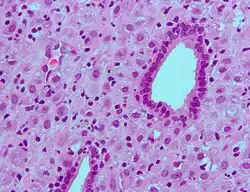

Молочные железы

Лобулоальвеолярное развитие

Прогестерон играет важную роль в развитии молочных желёз у женщин. Вместе с пролактином он опосредует лобулоальвеолярное созревание молочных желёз во время беременности, чтобы обеспечить выработку молока и грудное вскармливание потомства после родов. Эстроген стимулирует выработку рецепторов прогестерона в грудной ткани, поэтому прогестерон зависит от эстрогена в активации лобулоальвеолярного развития. Было установлено, что RANKL является критическим промежуточным медиатором вызываемого прогестероном лобулоальвеолярного созревания. Мыши с нокаутом RANKL демонстрируют почти идентичный фенотип молочной железы мышам с нокаутом рецептора прогестерона, включая нормальное развитие протоков молочной железы, но полное отсутствие развития лобулоальвеолярных структур.